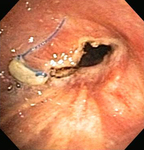

Post-lung transplant anastomotic bronchial stenosis: right mainstem anastomosis post-multimodal endoscopic therapy

From the collections of Jose Fernando Santacruz MD, FCCP, DAABIP and Erik Folch MD, MSc; used with permission